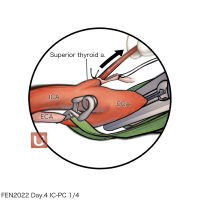

FEN2022シリーズ